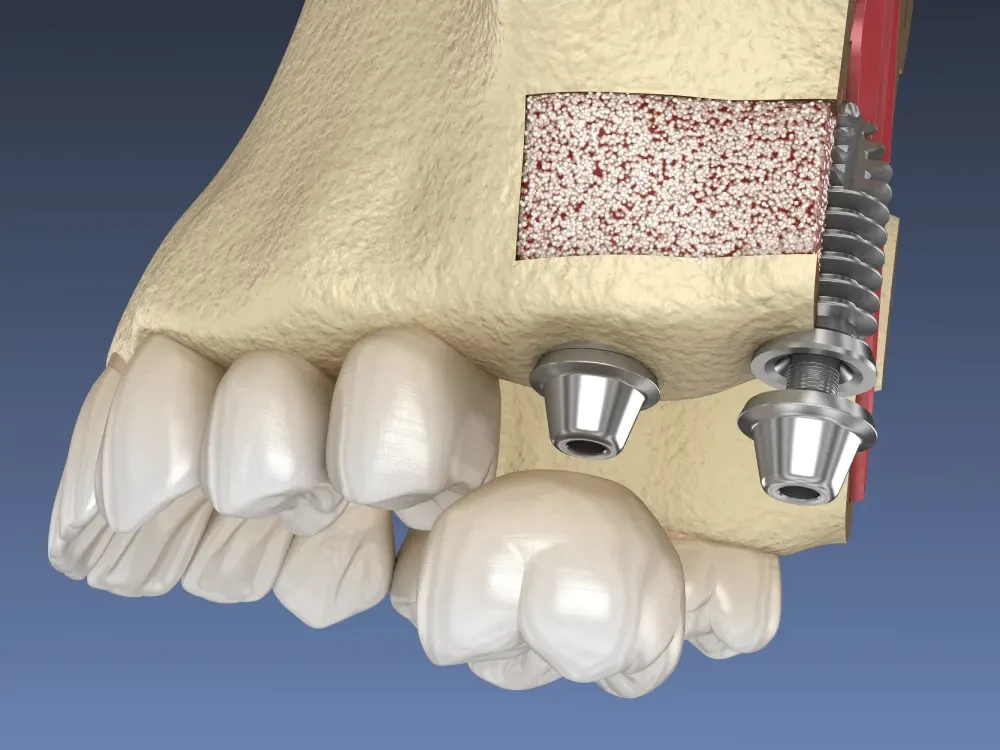

Сложная травма челюсти, долгое отсутствие одного или нескольких зубов, полная потеря зубов в пожилом возрасте – что общего у этих случаев?

Чаще всего во всех этих ситуациях костная ткань челюсти уменьшается в обьеме. Раньше единственным выходом в таком положении была костная пластика. Это сложная процедура, которая восстанавливает кость, но требует больших затрат и долгого восстановления.

Но современная стоматология дает возможность восстановить красивую и здоровую улыбку без этой процедуры – расскажем как.